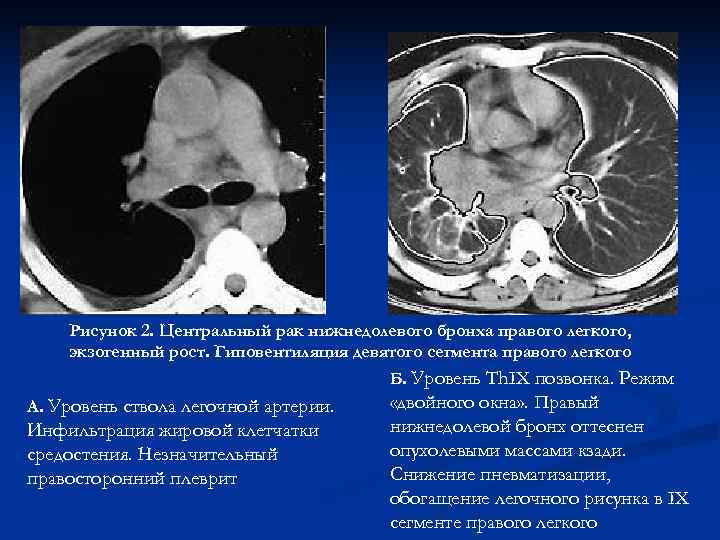

Рисунок 2. Центральный рак нижнедолевого бронха правого легкого, экзогенный рост. Гиповентиляция девятого сегмента правого легкого Б. Уровень Th. IX позвонка. Режим А. Уровень ствола легочной артерии. «двойного окна» . Правый Инфильтрация жировой клетчатки нижнедолевой бронх оттеснен средостения. Незначительный опухолевыми массами кзади. правосторонний плеврит Снижение пневматизации, обогащение легочного рисунка в IX сегменте правого легкого